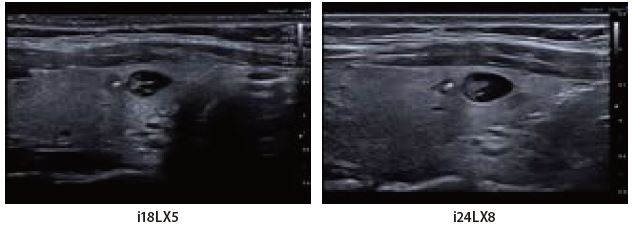

Випадок 1: Вузли щитоподібної залози

Це парні зображення пацієнта з гіпотиреозом і множинними напівкістозними/твердими вузлами.

Обидва датчики i-серії добре окреслюють внутрішні структури вузлів щитоподібної залози. Однак у датчика i24LX8 контур і межі меншого вузла чіткіші, і навіть при роботі на дуже високій частоті не відбувається втрати проникаючої здатності. Краща клінічна деталізація може допомогти в діагностиці та поліпшити класифікацію вузлових утворень щитоподібної залози.

Мал. 8.